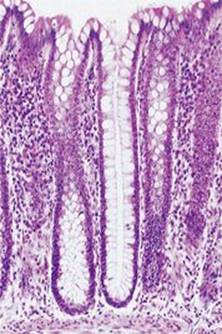

Glands are groups of epithelial cells that produce specialised secretions. Glands that discharge their secretion onto the epithelial surface of hollow organs, either directly or through a duct, are called exocrine glands. Exocrine glands vary considerably in size, shape and complexity as shown in Figure 3.24. Secretions of exocrine glands include mucus, saliva, digestive juices and earwax. Figure 3.25 shows simple tubular glands of the large intestine. Other glands discharge their secretions into blood and lymph. These are called endocrine glands (ductless glands) and their secretions are hormones (see Ch. 9).

Figure 3.25 Simple tubular glands in the large intestine. A stained photograph (magnified × 50).